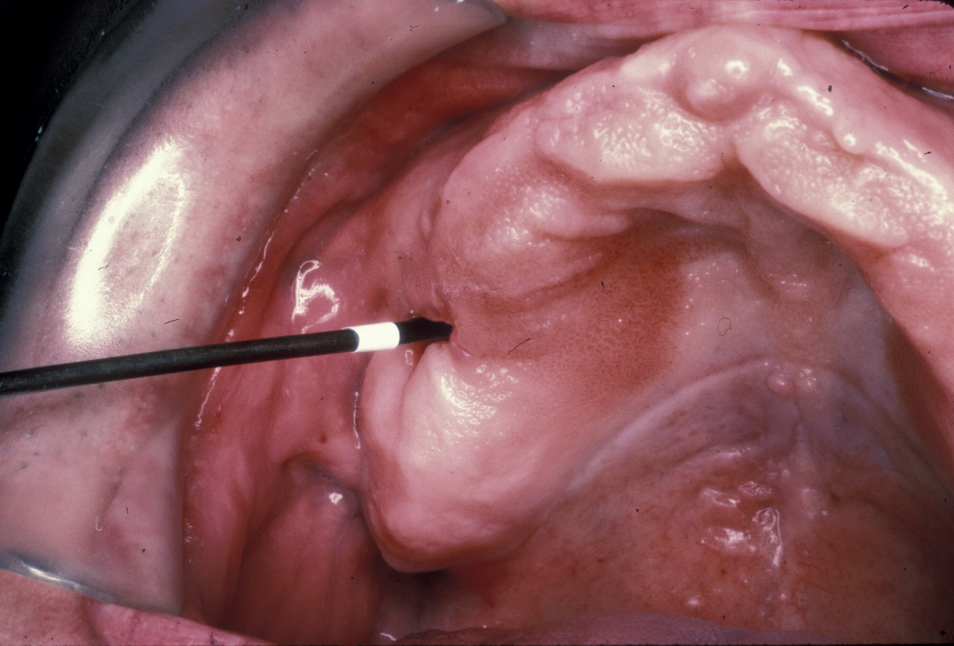

An established (chronic) oroantral fistula (Figure 3) leads to bouts of recurrent maxillary sinusitis, there may be a foul taste in the mouth, and fluids may be passing from the mouth through the fistula and out of the nose. The fistula can be demonstrated by occluding the nose and blowing out through the nose: air will be seen to bubble out of the fistula. A plain X-ray radiograph helps to identify any fragments of retained roots in the sinus.

Figure 3: Chronic oroantral fistula. Very rarely this can be a sign of an underlying malignancy.